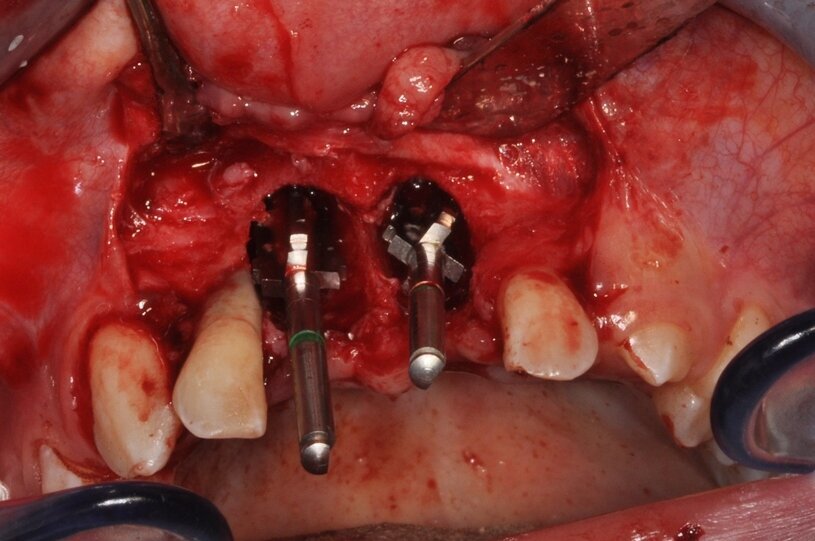

Miesiąc po ekstrakcji zębów przeprowadzono zabieg autotransplantacji (Ryc. 8). W znieczuleniu dożylnym krótkotrwałym i miejscowym nasiękowym 4 amp. 4% Ubistesin Forte nacięto płat pełnej grubości trapezowy od 12 do 22. Stwierdzono rozległy ubytek kostny o charakterze krateru, bez blaszki przedsionkowej. Wiertłem chirurgicznym i implantologicznym wykonano miejsce biorcze na donory (Ryc. 9). Kolejno usunięto zęby mleczne 75 i 85 oraz pobrano zawiązki zębów stałych 35 i 45 w fazie rozwoju korzenia R3/4 wg Moorresa. Wprowadzono na miejsce biorcze oraz całkowicie pokryto płatem, zszywając nierozpuszczalnym syntetycznym monofilamentem poliamidowym o rozmiarze 5,0 (Seralon®). Miejsce dawcze zaopatrzono gąbką kolagenową w kształcie stożka (Parasorb® Cone), (Ryc. 10). Po zabiegu zalecono Augmentin 1000 mg (2 x 1 tabl.), Ibuprofenum 200 mg (3 x 1 tabl.), Enterol (2 x 1 tabl.), Reparil (3 x 2 tabl.). Po 14 dniach usunięto szwy. Gojenie przebiegało bez powikłań. Kontrole radiologiczne i kliniczne przeprowadzono 1, 3, 6 (Ryc. 11), 12 i 18 miesięcy po zabiegu. Na czas leczenia pacjenta zaopatrzono płytka ortodontyczną uzupełniającą braki zębów 11 i 21.

Ryc. 9_Miejsce biorcze po wytworzeniu łoża.